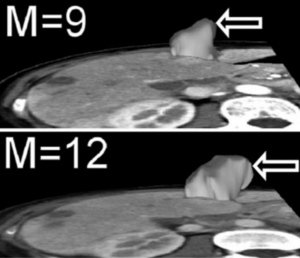

Publication: J Thorac Imaging. 2016 Jan;31(1):29-36. PMID: 26429588| PDF Authors: Zach JA, Williams A, Jou SS, Yagihashi K, Everett D, Hokanson JE, Stinson D, Lynch DA, COPDGene Investigators. Institution: Divisions of Radiology, Biostatistics and Bioinformatics, National Jewish Health, Denver, CO, USA. Background/Purpose: The purposes of this study were to evaluate the effect of smoking status on quantitative computed tomography CT measures of low-attenuation areas (LAAs) on inspiratory and expiratory CT and to provide a method of adjusting for this effect. Materials and Methods: A total of 6762 current and former smokers underwent spirometry and volumetric inspiratory and expiratory CT. Quantitative CT analysis was completed using open-source 3D Slicer software. Funding:

Examples of CN on CT. Coronal CT image of a GOLD 1 subject with moderately extensive visual extent of emphysema. However, the quantitative emphysema score was only 5.1%. The emphysema may have been masked on quantitative assessment by the presence of centrilobular nodules (circled) and patchy ground-glass abnormality (arrows). |